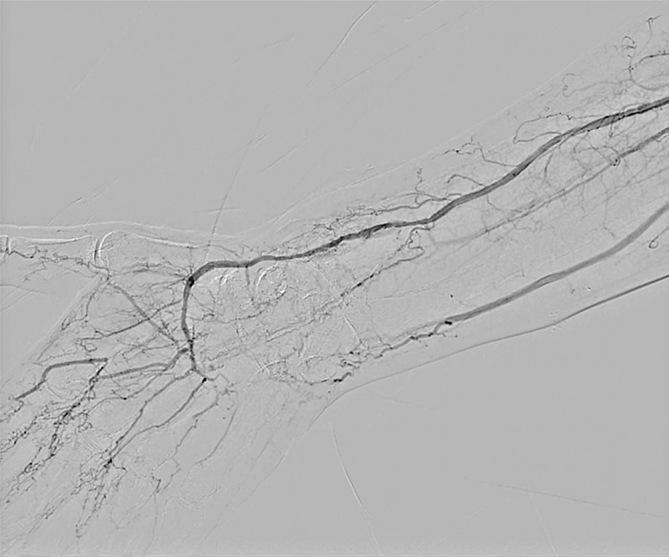

Kimura's disease is a lymphoproliferative disorder characterized by eosinophilic infiltration. Although it rarely causes peripheral arterial occlusive disease, its mechanism remains unclear. A 43-year-old man with a seven-year history of Kimura's disease, initially presenting with a cervical mass and treated with prednisolone, developed an ulcerative lesion from the right thumb to the middle finger. Ultrasonography revealed bilateral radial artery dilation and thrombosis. After he was diagnosed with Kimura's disease-associated vasculitis, he was treated with prostaglandin E1, warfarin, and cilostazol. Because of persistent symptoms, angioplasty was performed on the occluded radial artery. The patient's symptoms improved on the first postoperative day, with no re-occlusion observed after 2 years. Percutaneous transluminal angioplasty has been demonstrated as effective for early symptomatic relief in Kimura's disease.

木村病是一种以嗜酸性粒细胞浸润为特征的淋巴增生性疾病。虽然它很少引起外周动脉闭塞性疾病,但其发病机制仍不清楚。一名患有木村病7年的43岁男性,最初表现为颈部肿块,接受泼尼松龙治疗,随后右手拇指至中指出现溃疡性病变。超声检查显示双侧桡动脉扩张和血栓形成。在被诊断为木村病相关血管炎后,他接受了前列腺素E1、华法林和西洛他唑治疗。由于症状持续存在,对闭塞的桡动脉进行了血管成形术。患者术后第一天症状改善,2年后未观察到再闭塞。经皮腔内血管成形术已被证明对木村病的早期症状缓解有效。